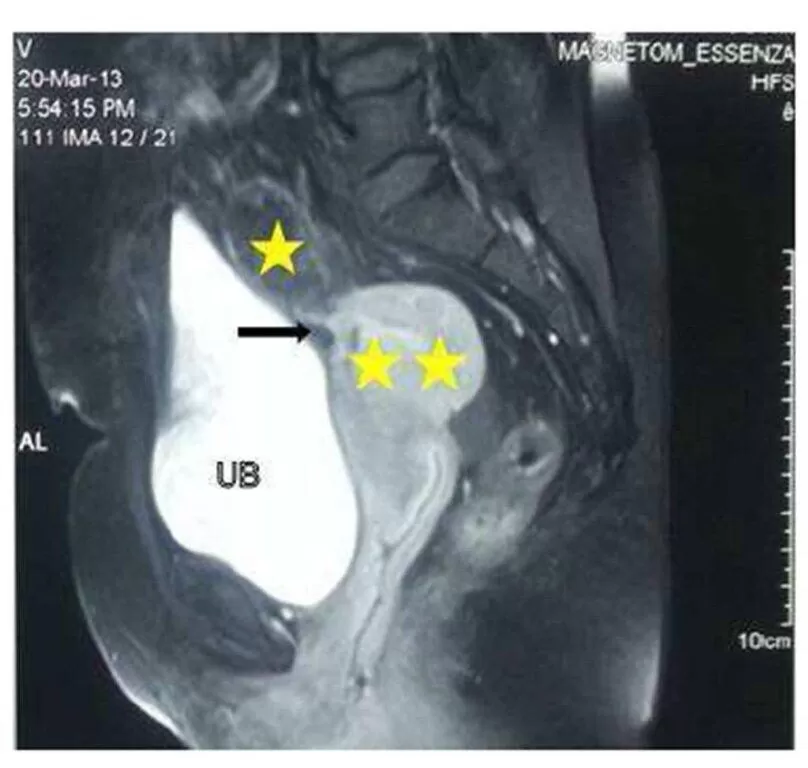

Barium enema (Fig.2 A & B) demonstrated luminal narrowing with irregularity of the wall of proximal sigmoid colon at the site suspected of presence of fistulous communication on HSG. Sagittal-T2 weighted MR image showed thinning of myometrium in the anterior wall with the presence of ill-defined fat plane and adjacent sigmoid loop attached to the anterior surface of the uterus (Fig.3). It indicated the site of the fistulous tract.

Figure 3:  Sagittal T2 weighted MRI showing retroverted uterus (double asterisks) with presence of proximal sigmoid loop (single asterisk) in close approximation to anterior aspect of uterine body with loss of intervening fat plane (arrow). UB: Urinary bladder.